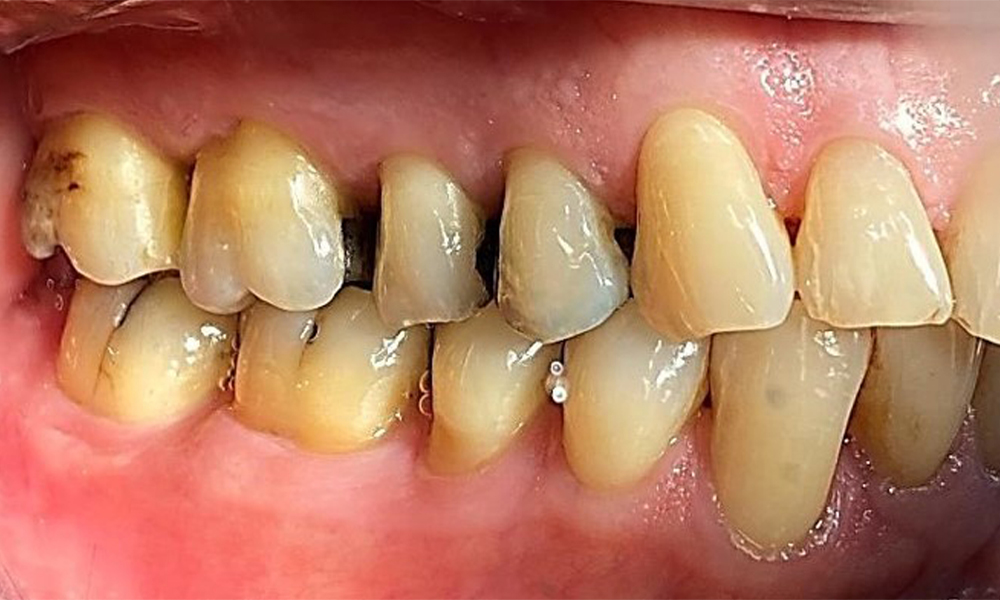

Right lateral view. Loss of the interdental papillae.

Fig. 3 Right lateral view. Loss of the interdental papillae. © Dr R. Krapf

The patient has stage II, grade B periodontitis (5). At 1 to 3 mm, the clinical probing depths were within the physiological range. Localized probing depths of 5 mm were observed on the mesiopalatal aspects on both 17 and 27. There are generalized recessions of 1–3 mm with partial loss of the interdental papillae (Fig. 2, Fig. 3, Fig. 4)